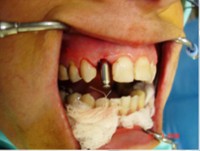

- Implante imediato

- Carga imediata

- Coroa protética cerâmica imediata